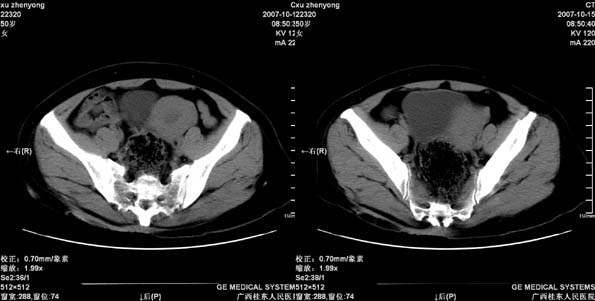

患者,女 50岁.会阴部坠胀感一月余,有痔疮病史,近期有便血;患者今年5月分结肠镜检查未见异常(由于患者不愿意ct增强扫描)没做增强,现准备手术,请各位老师会诊.

直肠壁明显增厚,呈块状表现,肠腔狭窄闭塞,考虑ca

直肠壁增厚明显,周围脂肪间隙模糊,见有小淋巴结显示,前方与阴道后壁分解不清。考虑直肠癌可能性大

不做强化,但平扫保留灌肠一定要做好。现在看直肠壁增厚明显,周围脂肪间隙模糊,前方与阴道后壁分界不清。考虑直肠癌可能性大

直肠下端及肛门周围可见软组织改变,如果5月份检查的结肠镜结果可靠,那么本病例痔的可能性还是很大的。肿瘤生长的不会如此之快。

直肠左侧壁明显增厚,考虑直肠癌可能性大.